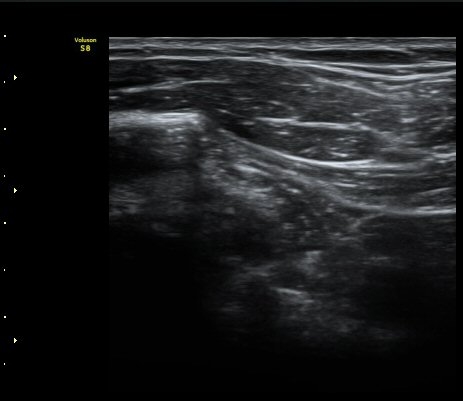

ÃÊÀ½ÆÄ °Ë»ç

À̵ιڱ٠Á¾´Ü¸é°Ë»ç»ó ƯÀÌ ¼Ò°ßÀ» º¸ÀÌÁö ¾ÊÀ¸³ª(±×¸² 1)  ŽÃËÀÚ¸¦ ¾Æ·¡·Î À̵¿ÇÏ´Ï

°ß°©ÇÏ±Ù°Ç ³»Ãø¿¡¼­ ¼ö¾×Àú·ù°¡ °üÂûµÈ´Ù(±×¸² 2).